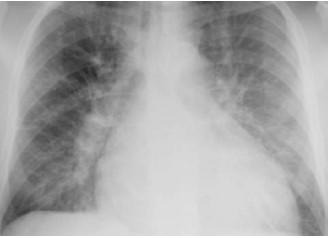

Segue radiografia de tórax.